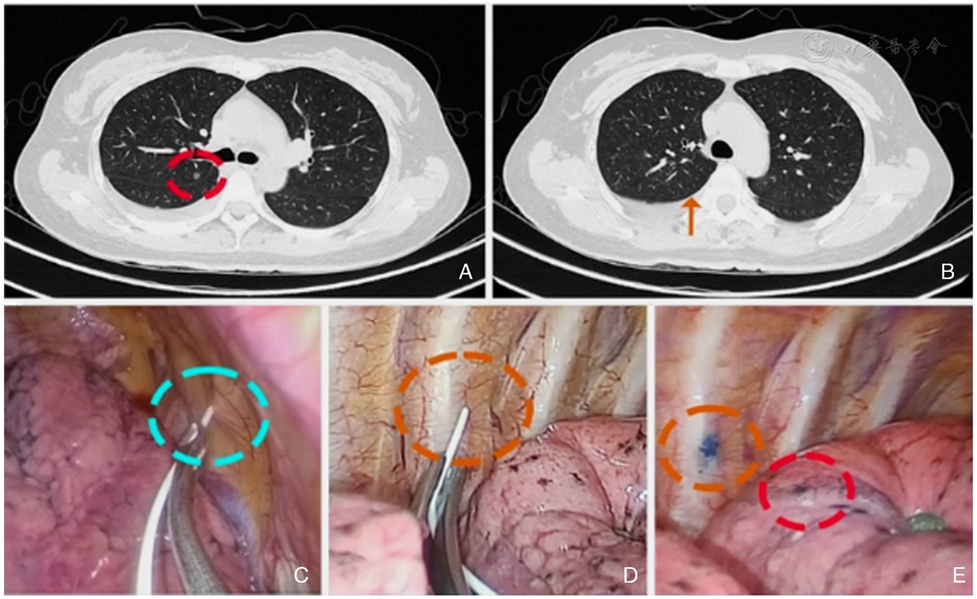

图1 TMPGL

图2 右上肺结节使用TMPGL

图3 免穿刺全域定位方法用于叶裂内结节

图4 纵隔面结节定位较为困难

术前采用平卧位或侧卧位CT并进行三维重建规划,选取第1肋胸骨肋关节、第4肋肋椎关节及第7肋肋椎关节作为骨性标记点;CT引导下穿刺定位也一并完成。术中利用磁导航探头触碰骨性标记校准空间坐标,引导至胸壁虚拟定位点并涂抹染料(亚甲蓝);膨肺后染料被动转印至脏层胸膜,最终实现肺结节定位。

Preoperative CT scanning was performed in the supine or lateral position, followed by 3D reconstruction to develop the strategy and plan the approach. The first rib-sternocostal joint, the fourth rib-vertebra joint, and the seventh rib-vertebra joint were selected as bony landmarks. CT-guided puncture localization was also performed. Intraoperatively, spatial coordinates were calibrated by touching the bony landmarks with a magnetic navigation probe, which then guided the probe to a virtual localization point on the chest wall where methylene blue dye was applied. After lung inflation, the dye was passively transferred to the visceral pleura, thereby achieving accurate localization of the lung nodule.